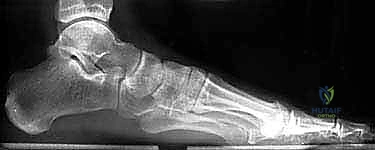

- الأشعة السينية (X-rays) متعددة الزوايا: لتقييم الانهيار العظمي وزوايا الكعب (مثل زاوية بوهلر وزاوية جيسان).

| ارتفاع الكعب (زاوية بوهلر) | طبيعي (20 إلى 40 درجة)، يدعم قوس القدم | منهار (زاوية مسطحة أو سلبية)، تسطح شديد للقدم |